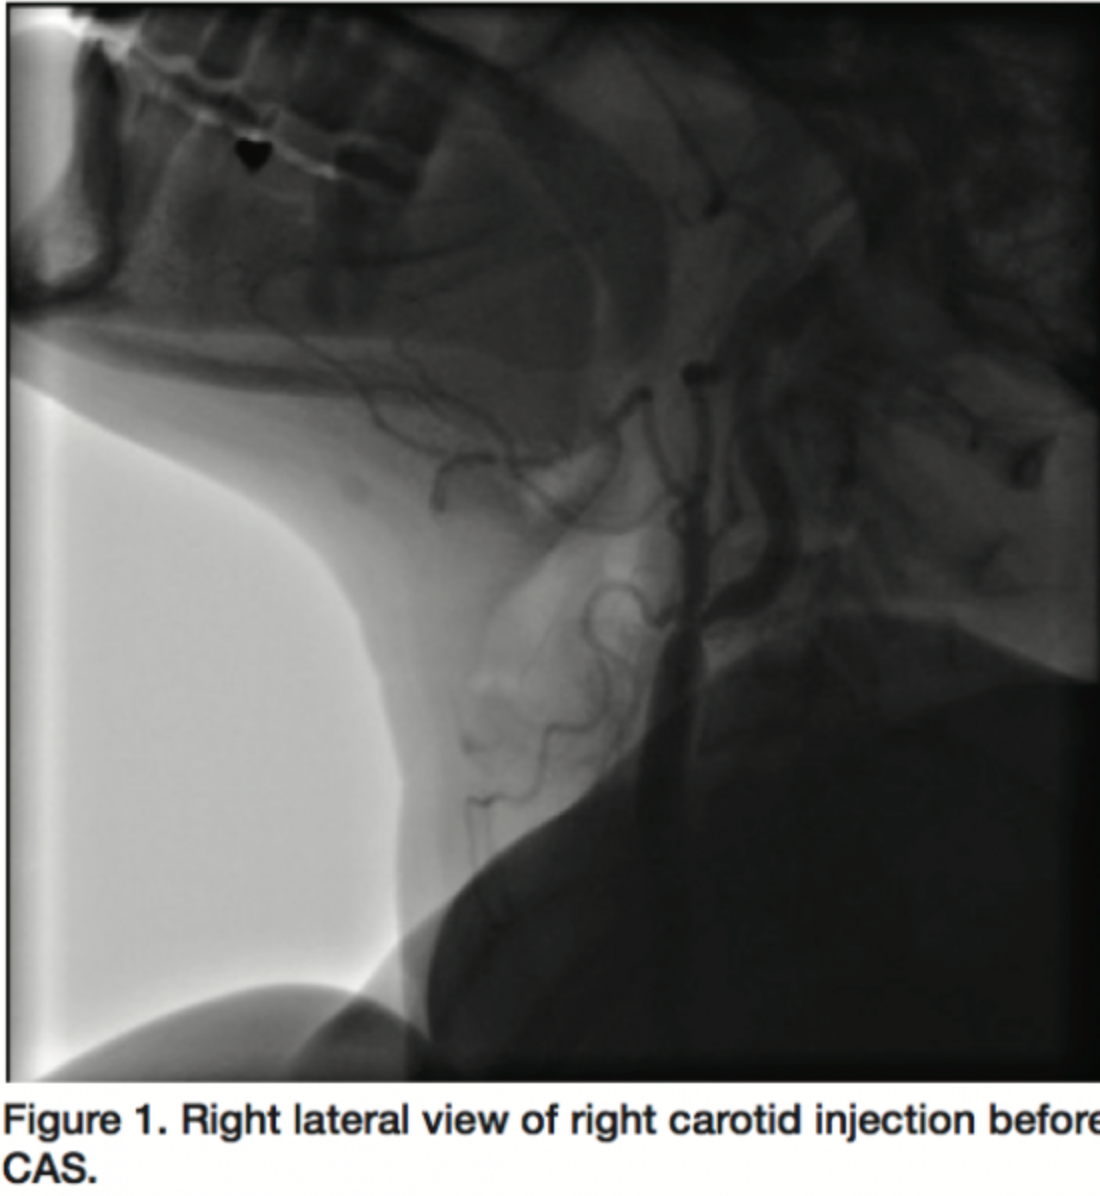

A 51-year-old female patient with history of diabetes mellitus, hypertension, hyperlipidemia and 3-vessel disease with left ventricular ejection fraction (LVEF) of 55% was a good candidate for coronary artery bypass graft (CABG) due to refractory chest pain. We proceeded with stenting of the right internal carotid because of a calcified plaque with 90% stenosis proximal to the right internal carotid without bulb involvement (Figures 1 and 2). The left internal carotid had a plaque with <50% stenosis. Her blood pressure was 120/80 before the procedure but she had severe prolonged hypotension (70 mmHg/p) after the procedure. By treatment with saline and dopamine, her blood pressure preserved about 120 to 130 mmHg but with a modest decrease in dose of dopamine (decreasing from 15 µg/kg/min to 12 µg/kg/min over 5 days); systolic blood pressure (SBP) dropped to 80 mmHg. This situation took 7 days and improved only after tight control of her blood sugar. Fasting blood sugar (FBS) was 96 mg/dL before and remained high despite divided doses of regular insulin (Table 1).